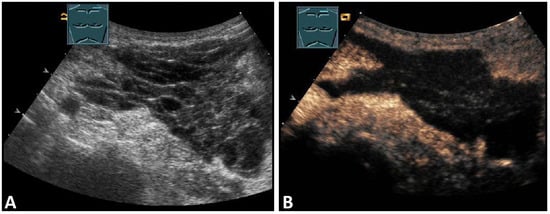

The thickness increase during inspiration was also used as a measure of muscle contraction. In most studies, an increase during inspiration of >20% is considered as normal [55] (Figure 31).

Figure 31.

Representation of diaphragm thickness in expiration (A) and inspiration (B) in pleural effusion (PE) and ascites (As).

3.3.2. Diaphragm Excursion

Diaphragmatic excursion is measured in M-mode US with a low-frequency probe (2.5–5.0 MHz) in an anterior subcostal view through the liver window. The transducer should be positioned between the middle clavicular line and the anterior axillary line and directed medially, cranially, and dorsally to visualize the posterior third of the right diaphragm, approximately 5 cm lateral to the inferior vena cava foramen [52,53]. The amplitude (distance between the highest and the lowest points of the diaphragmatic movement) and the speed are measured in both quiet breathing and forced inspiration (the sniff maneuver) (Figure 32) [52,53]. The amplitude of diaphragmatic excursion is highly dependent on physical constitution and ranges from approximately 1–2 cm (resting breathing) to 7–9 cm (forced breathing) [59]. The diaphragm excursion can be determined only in spontaneously breathing patients.

Figure 32.

Illustration of diaphragmatic motility during quiet (A) and deep breathing (B) in a subcostal view.